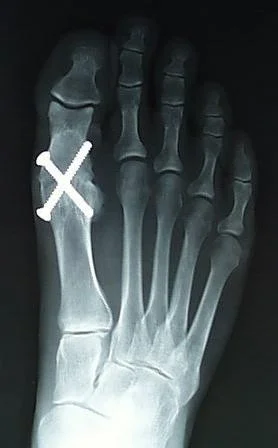

Arthrodesis / Fusion

- Arthrodesis / Fusion:

- Stabilizing the joint to make it painless

- Indicated:

- Loss of key muscles, Painful ankylosed joint in young patient, Failed previous total joint arthroplasty

- Contraindication:

- Active infection

- Adjacent joint or contralateral joint OA

- Used:

- Hand, Elbow, Shoulder, Spine, Ankle & foot

- Less likely in Hip & knee